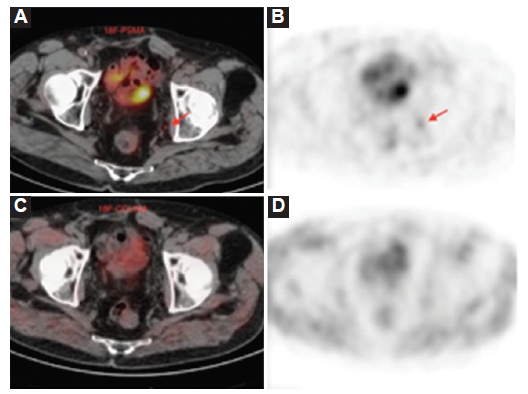

El PSA disparador de la PET/TC mostró una mediana (Q1-Q3) de 3,14 (0,73-8,69) ng/ml. La PET/TC colina mostró una tasa de positividad del 35%, mientras que la PET/TC 18F-PSMA mostró una tasa de positividad del 80%, pero con un PSA disparador ≥ 2 ng/dl la PET/TC 18F-PSMA tuvo un 100% de positivos; mientras que la PET/TC 18F-colina un 55% positivos (Figs. 1, 2 y 3). De las 35 PET/TC 18F-colina negativas, 24 (69%) fueron positivas con PET/TC 18F-PSMA. Todos los PET/TC 18F-colina positivos también fueron positivos con PET/TC 18F-PSMA.

En la valoración de las cinéticas de PSA para PET/TC 18F-PSMA las curvas ROC mostraron para PSAV un área bajo la curva (AUC) de 0,93 (IC 95%: 0,83-1; p = 0,0001) presentado el punto de corte de 0,85 ng/ml/año una sensibilidad del 88% y una especificidad del 87%. El 97% de las PET/TC 18F-PSMA fueron positivas, con un PSAV > 0,85 ng/ml/año (p = 0,0001), mientras que las curvas ROC mostraron para PSADT un AUC de 0,38 (IC 95%: 0,21-0,57; p = 0,321) sin evidenciar valor diagnóstico con significancia estadística (Fig. 4).